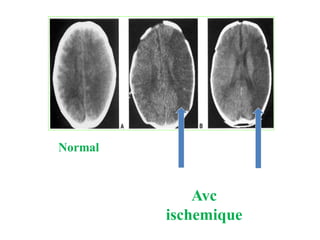

SIGNES DIRECT

Sur la TDM on voit une HYPODENSITE

intéressant le territoire artérielle atteint

Normal

Avc

ischemique